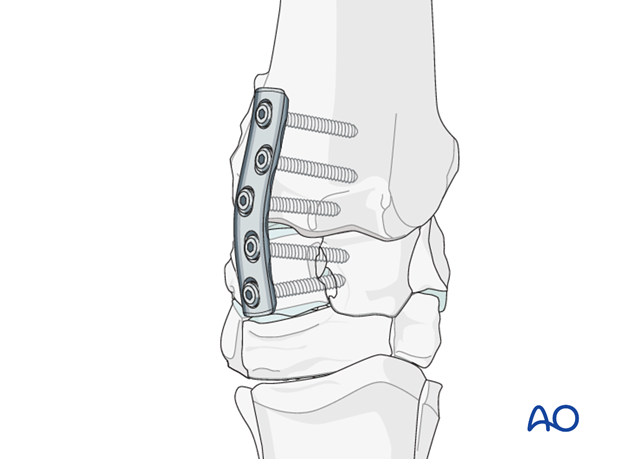

The plates are normally located craniomedially and craniolaterally over the intermediate and radial carpal bones of the proximal row. Occasionally, the plates will be placed over the intermediate and ulnar carpal bones if marked realignment of the limb is necessary.

Once sufficient compression is achieved using the tension device in the first plate, the remaining screws are inserted into the radial carpal bones.

The tension device is removed and the second plate is attached using appropriate dynamic compression or locking plate principles.

Radiographs are taken after all screws are inserted to assure that all screws are in the proper location and the joint is been well reduced.